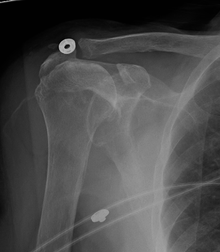

A complete tear of the supraspinatus resulting in a shift upwards of the head of the humerus

Diagnosis is based upon physical assessment and history, including description of previous activities and acute or chronic symptoms. A systematic, physical examination of the shoulder comprises inspection, palpation, range of motion, provocative tests to reproduce the symptoms, neurological examination, and strength testing.[15] The shoulder should also be examined for tenderness and deformity. Since pain arising from the neck is frequently 'referred' to the shoulder, the examination should include an assessment of the cervical spine looking for evidence suggestive of a pinched nerve, osteoarthritis, or rheumatoid arthritis.

Diagnostic modalities, dependent on circumstances, include X-ray, MRI, MR arthrography, double-contrast arthrography, and ultrasound. Although MR arthrography is currently considered the gold standard, ultrasound may be most cost-effective.[16] Usually, a tear will be undetected by X-ray, although bone spurs, which can impinge upon the rotator cuff tendons, may be visible.[17] Such spurs suggest chronic severe rotator cuff disease. Double-contrast arthrography involves injecting contrast dye into the shoulder joint to detect leakage out of the injured rotator cuff[18] and its value is influenced by the experience of the operator. The most common diagnostic tool is magnetic resonance imaging (MRI), which can sometimes indicate the size of the tear, as well as its location within the tendon. Furthermore, MRI enables the detection or exclusion of complete rotator cuff tears with reasonable accuracy and is also suitable to diagnose other pathologies of the shoulder joint.[19]

The logical use of diagnostic tests is an important component of effective clinical practice.[20] X-rays cannot directly reveal tears of the rotator cuff, a 'soft tissue', and consequently, normal X-rays cannot exclude a damaged cuff. However, indirect evidence of pathology may be seen in instances where one or more of the tendons have undergone degenerative calcification (calcific tendinitis). Also, large tears of the rotator cuff may allow the humeral head to migrate upwards (high-riding humeral head) which may be visible on X-ray. Prolonged contact between a high-riding humeral head and the acromion above it, may lead to X-rays findings of wear on the humeral head and acromion and secondary degenerative arthritis of the glenohumeral joint (the ball and socket joint of the shoulder), called cuff arthropathy, may follow.[21] Incidental X-ray findings of bone spurs at the adjacent acromioclavicular joint may show a bone spur growing from the outer edge of the clavicle downwards towards the rotator cuff. Spurs may also be seen on the underside of the acromion, once thought to cause direct fraying of the rotator cuff from contact friction, a concept currently regarded as controversial.